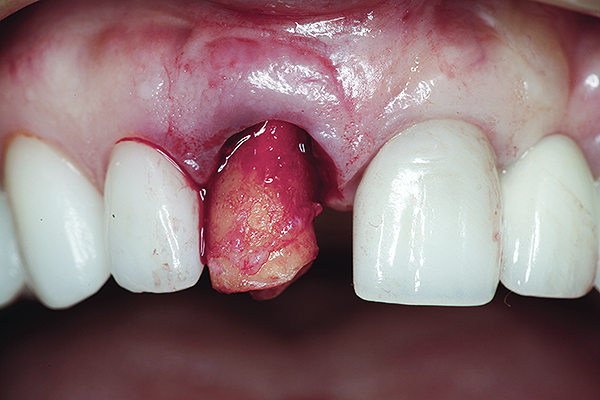

Fig 3. The root tip, after removal of the crown.

Figure 3

Fig 4. The root was atraumatically extracted using periotomes.

Figure 4

Without reflecting a full-thickness mucoperiosteal flap, the root tip was carefully extracted using periotomes to preserve the buccal plate and interproximal bone (Figure 3 and Figure 4). The extraction site was carefully debrided, and an osteotomy was prepared following the manufacturer’s instructions for placement of a 5/4mm D x 13mm L OSSEOTITE® Tapered Certain® PREVAIL® Implant (BIOMET 3i, www.biomet3i.com).